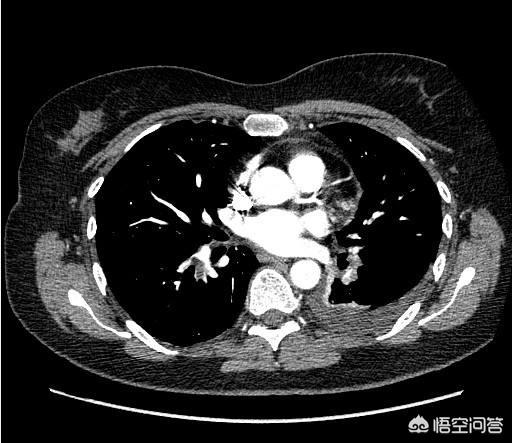

Dépistage du cancer du poumonRadiographie du thorax et/ou tomodensitométrie améliorée du thorax.

La radiographie thoracique, simple, économique et rapide, est couramment utilisée pour les examens médicaux. Pour les personnes âgées de plus de 45 ans, ayant des antécédents de tabagisme ou des antécédents familiaux de cancer du poumon, il est recommandé d'effectuer une tomodensitométrie spiralée en couche mince, qui offre une résolution élevée et permet de détecter de petits foyers de cancer dans les poumons. Lorsque des nodules pulmonaires sont découverts sur les radiographies du thorax, un scanner plus poussé est généralement nécessaire pour clarifier la situation, et une ponction-biopsie est nécessaire pour clarifier la situation en cas de forte suspicion de cancer du poumon.